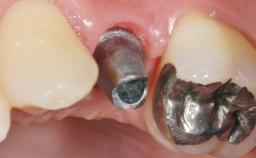

Early Placement of an Implant in a Maxillary Right Central Incisor Site

This 41-year-old female patient was referred to the clinic for the replacement of the right central incisor, since the tooth had developed a root fracture in the long axis that made extraction necessary. The healthy, non-smoking patient was first seen with the tooth still in place. A detailed Esthetic Risk Assessment was performed.The patient was worried about her dental esthetics and had high expectations for a successful treatment outcome from an esthetic point of view. The patient had a medium lip line that displayed parts of the gingiva in the anterior maxilla upon smile.

| Abutment Type | Customized |